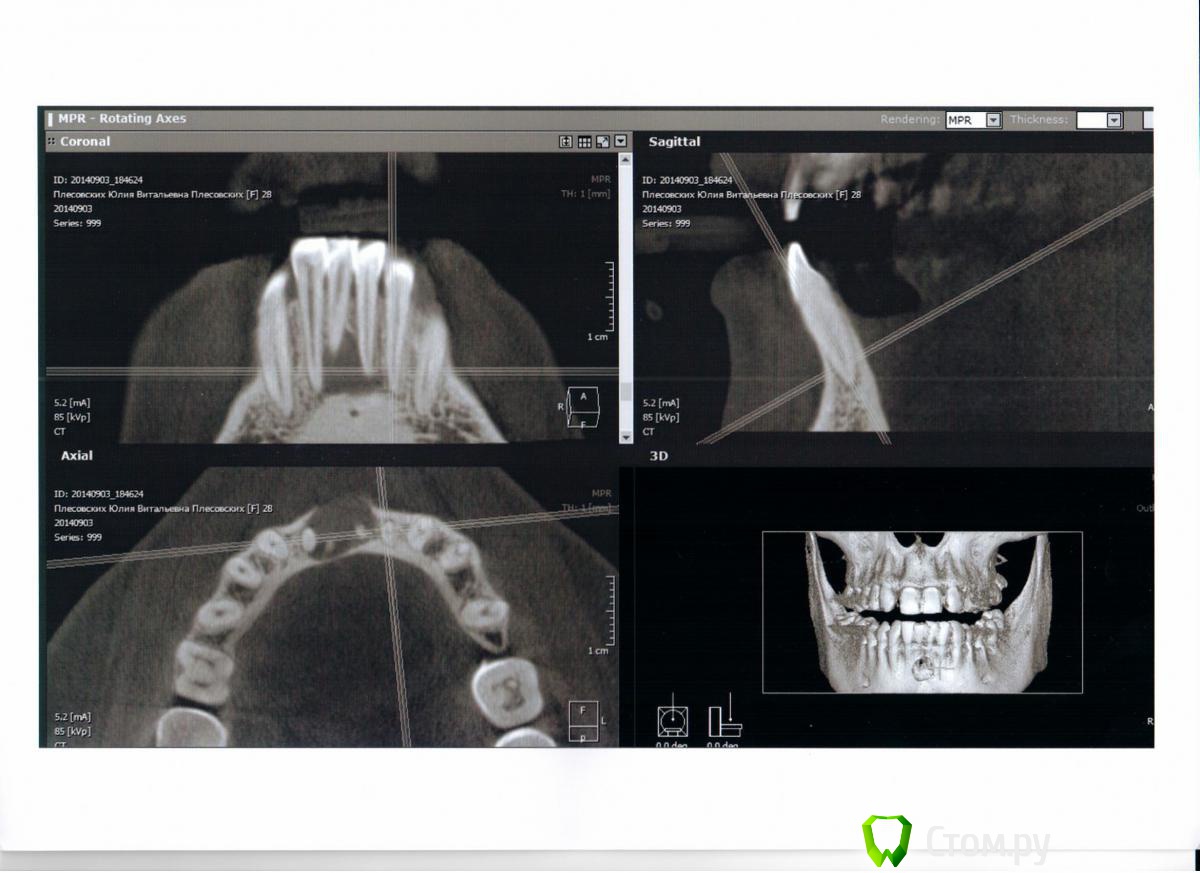

Julia_86 Опубликовано 9 сентября, 2014 Поделиться Опубликовано 9 сентября, 2014 Здравствуйте, прошу совета по дальнейшему лечению. Не знаю верно ли разместила тему, поправьте если что не так.Месяца полтора назад случайно обнаружилась радикулярная киста нижних передних зубов. Хотела поставить брекеты по причине адентии верхних двоек, врач отравил на понорамный снимок - увидели кисту. Зубы, которые охвачены кистой, никогда не болели, но один из зубов изменен в цвете и видимо был травмирован,т.к. видно скол. Терапевт сначала хотела лечить через каналы, закладывая лекарство на полгода, но я засомневалась и пошла к хирургу. Хирург отправила на КТ. В итоге хирург после КТ решила, что центральный резец в кисте нужно удалять(он короче всех) и делать операцию одновременно. Во время операции заложить костнозамещающий материал (bio-oss) и ждать пока все восстановиться.Но есть один момент - чтобы остальные 2 зуба, которые в кисте, не выпали, врач предлагает или поставить брекеты перед операцией, чтобы они не давали зубам шевелиться после операции. Позже, когда все зарастет и костная ткань восстановиться - брекетами восстановить зубной ряд из 3х резцов. Сейчас на нижней челюсти скученность, после удаления как раз хватит места для 3х зубов. Либо до операции клеить какую-то штуку на внутреннюю сторону зубов и после операции через 4 месяца протезировать. Зубы, которые в кисте будут депульпированы и запломбированы. Подскажите, какой вариант более целесообразен. Ссылка на комментарий

dr-krasnov Опубликовано 9 сентября, 2014 Поделиться Опубликовано 9 сентября, 2014 Это не радикулярная киста. Стоит подумать о дисплазии. Что скажут коллеги? 1 1 Ссылка на комментарий

Bier Опубликовано 10 сентября, 2014 Поделиться Опубликовано 10 сентября, 2014 Автор, сфотографируйте нижние зубы пожалуйста.Не надо торопиться с хирургией.План действий такой: определить витальные (живые) ли зубы, находящиеся в полости кисты. Скорее всего потемневший зуб мертв. Тогда надо провести терапевтическое лечение, через канал, желательно только терапевта поискать с микроскопом.Если все зубы живые, как предположил коллега, тогда к хирургу с обязательной гистологией образования. 1 Ссылка на комментарий